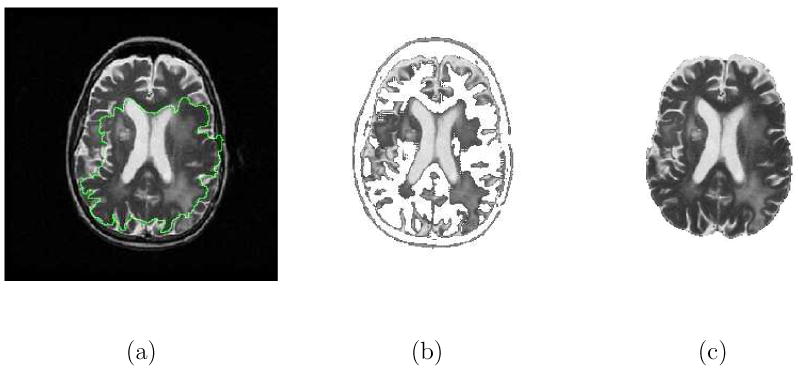

The Caselles-Malladi deformable contour notably improved the initialization of parametric active contours provided that the initial contour was placed symmetrically with respect to the boundaries of interest [12,13]. In practice, this is not easy to achieve since many medical image segmentation problems are not dealing with regularly shaped objects. Fig. 1 demonstrates the difficulty of using the Caselles-Malladi deformable contour to segment the brain with convoluted shapes in T2-weighted MR images. Note that the initial contour was not symmetrically placed with respect to the brain. It was not easy to choose an appropriate stopping force required to achieve satisfactory results. The contour was confined inside by the high intensity structures when using a stronger stopping force and the contour leaked past the brain boundaries when using a weaker stopping force [see (1)].

Fig. 1.

Difficulty of using the Caselles-Malladi deformable contour in segmenting the brain in T2-weighted MR images. (a) The initial contour that was not symmetrically placed. (b) The contour was confined inside the brain by the inner high intensity structures using a strong stopping force. (c) Some of the contour were crossed over the brain boundaries while some contours were restricted inside, using a slightly weaker stopping force. (d) The contour leaked past the brain boundaries using a weaker stopping force.